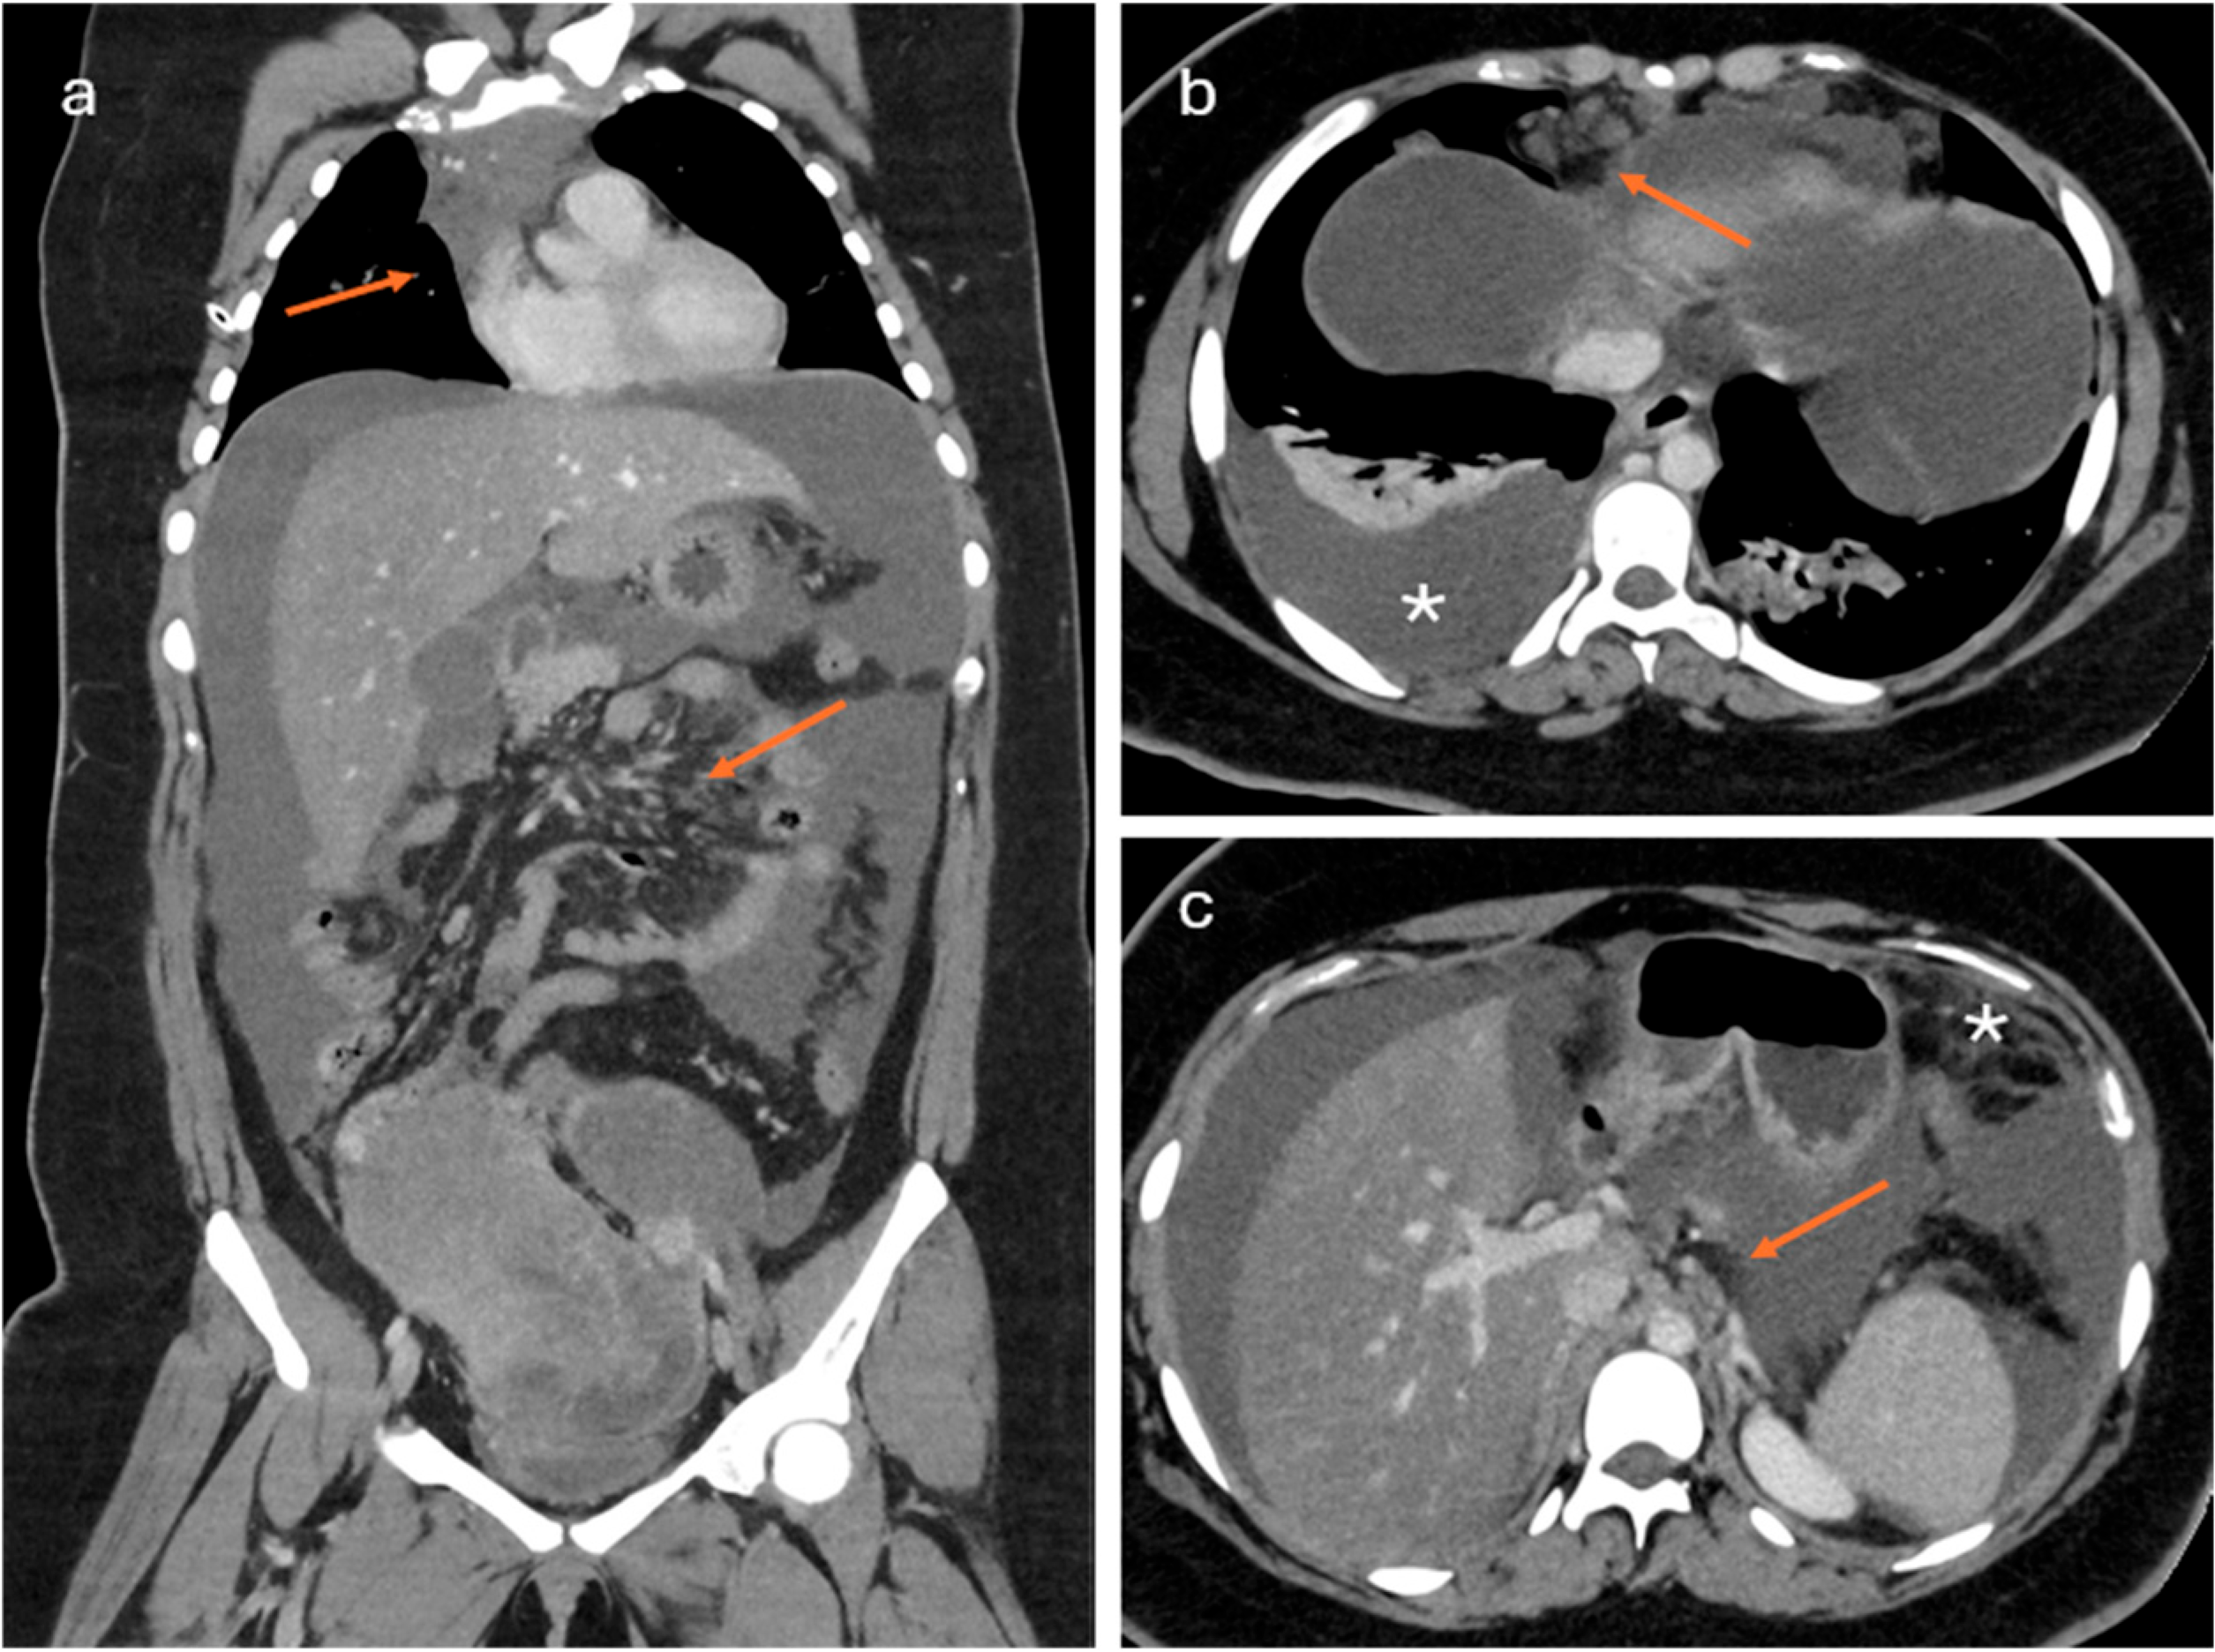

2.2. CT Imaging

- Lesions associated with the presence of peritoneal implants and/or secondary disease localization (Figure 6)

- Chiu, S.; Tsitsiou, Y.; Da Silva, A.; Qin, C.; Fotopoulou, C.; Rockall, A. CT and MRI in Advanced Ovarian Cancer: Advances in Imaging Techniques. Korean J. Radiol. 2025, 26, 841. [Google Scholar] [CrossRef] [PubMed]

- Rizzo, S.; Avesani, G.; Panico, C.; Manganaro, L.; Gui, B.; Lakhman, Y.; Andrieu, P.C.; Bharwani, N.; Rockall, A.; Thomassin-Naggara, I.; et al. Ovarian cancer staging and follow-up: Updated guidelines from the European Society of Urogenital Radiology female pelvic imaging working group. Eur. Radiol. 2025, 35, 4029–4039. [Google Scholar] [CrossRef]

- Avesani, G.; Arshad, M.; Lu, H.; Fotopoulou, C.; Cannone, F.; Melotti, R.; Aboagye, E.; Rockall, A. Radiological assessment of Peritoneal Cancer Index on preoperative CT in ovarian cancer is related to surgical outcome and survival. Radiol. Med. 2020, 125, 770–776. [Google Scholar] [CrossRef] [PubMed]